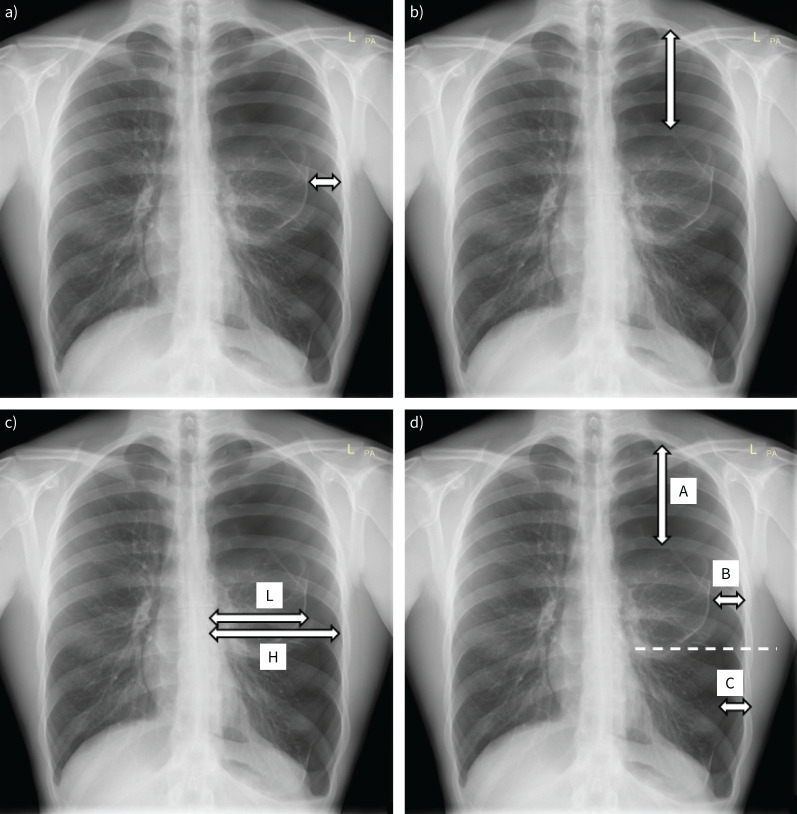

FIGURE 6.

Different methods of measuring pneumothorax size on chest radiographs. a) Size is assessed based on the distance between the visceral pleura and chest wall on the level of the hilum; if ≥2 cm big pneumothorax is diagnosed. b) Size is measured in the apex; if ≥3 cm big pneumothorax is diagnosed. c) Light index assesses pneumothorax volume V(%)=(1−L3/H3)×100, where L is the diameter of collapsed lung and H is the diameter of the hemithorax on a chest radiograph. d) Collins formula: V=4.2+(4.7×(A+B+C)), uses three interpleural distances measured at specified points (A, B and C) to assess the volume of pneumothorax.

Depending on the size of pneumothorax, the lung may be completely compressed, and in cases of tension pneumothorax the mediastinum may be shifted to the contralateral side. Sometimes air may accumulate in other areas of the chest cavity as presented in figure 7. A sign that indirectly suggests the presence of air in the pleural cavity is a straight fluid horizontal line (figure 7), appearing when there is fluid and air in pleural space (hydropneumothorax).

In the case of a supine patient, air is most visible at the lung bases, increasing the lucency over the upper abdomen. Therefore, pneumothorax should be suspected when there is a sharp demarcation of the cardiac and mediastinal interfaces in anteromedial recess or there is a deep sulcus sign, double diaphragm sign or when subcutaneous gas is present in nonpenetrating trauma patients (figure 7) [60, 61]. Chest radiography in lateral decubitus position may show a small pneumothorax (15 mL of air) [62]. One should not forget about situations that may mimic pneumothorax (for details see table 1). Different formulas allow quantification of pneumothorax size and the making of therapeutic decisions (figure 6) [58, 63, 64].